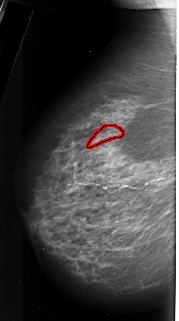

A_1019_1.LEFT_MLO

FILE: A_1019_1.LEFT_MLO.OVERLAY

TOTAL_ABNORMALITIES 1

ABNORMALITY 1

LESION_TYPE CALCIFICATION TYPE PLEOMORPHIC DISTRIBUTION LINEAR

ASSESSMENT 4

SUBTLETY 3

PATHOLOGY MALIGNANT

TOTAL_OUTLINES 1

BOUNDARY